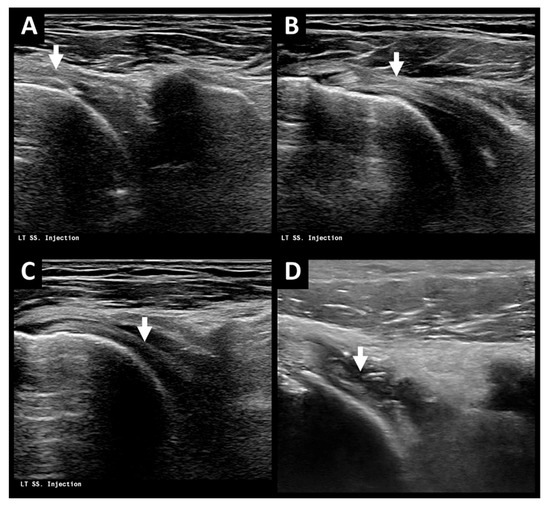

2.2. Treatment Process